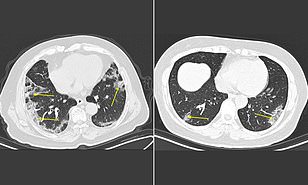

CT provides best diagnosis for COVID-19

Date:February 26, 2020

Source:Radiological Society of North America

Summary:In a study of more than 1,000 patients published in the journal Radiology, chest CT outperformed lab testing in the diagnosis of 2019 novel coronavirus disease (COVID-19). The researchers concluded that CT should be used as the primary screening tool for COVID-19.

Chest CT, a routine imaging tool for pneumonia diagnosis, is fast and relatively easy to perform. Recent research found that the sensitivity of CT for COVID-19 infection was 98% compared to RT-PCR sensitivity of 71%.

Recent research found that the sensitivity of CT for COVID-19 infection was 98% compared to RT-PCR sensitivity of 71%.

For the current study, researchers set out to investigate the diagnostic value and consistency of chest CT imaging in comparison to RT-PCR assay in COVID-19.

The sensitivity of chest CT in suggesting COVID-19 was 97%, based on positive RT-PCR results. In patients with negative RT-PCR results, 75% (308 of 413 patients) had positive chest CT findings. Of these, 48% were considered as highly likely cases, with 33% as probable cases. By analysis of serial RT-PCR assays and CT scans, the interval between the initial negative to positive RT-PCR results was 4 to 8 days.

“About 81% of the patients with negative RT-PCR results but positive chest CT scans were re-classified as highly likely or probable cases with COVID-19, by the comprehensive analysis of clinical symptoms, typical CT manifestations and dynamic CT follow-ups,” the authors wrote.

(e.d. no surprise here for those following on the thread.... will have to look at new WHO requirements as today he said there would be some coming out)